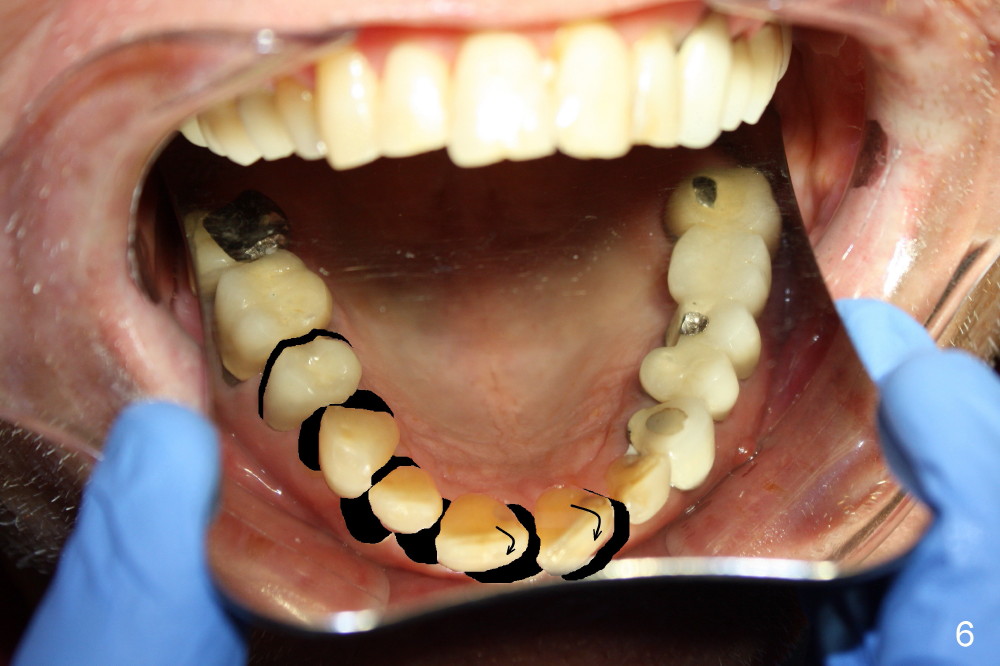

Although there is apical infection associated with the upper left first bicuspid (Fig.3 *), orthodontic treatment consists of extraction of a single tooth: the upper right first bicuspid (Fig.4,5: x), minor movement of the posterior teeth (Fig.4,5 smaller arrow) and major movement of the anterior teeth (bigger arrow). Fig.6 shows simulated tooth movement.